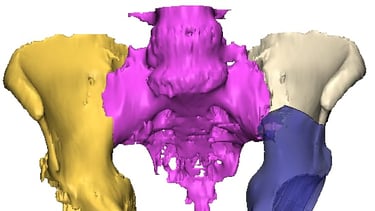

Galería Médica

Imágenes de procedimientos y técnicas en cirugía de cadera.